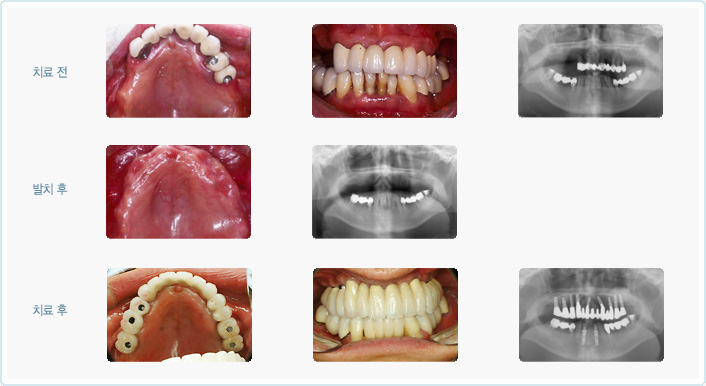

| ÀÓÇöõÆ®´Â ÀÚ½ÅÀÇ »À¿¡ Àΰø Ä¡¾Æ¸¦ ¸¸µé°Ô µÇ´Â °ÍÀ̹ǷΠÀûÀýÇÑ ¾çÀÇ »À°¡ ÀÖ¾î¾ß¸¸ °¡´ÉÇÕ´Ï´Ù. »À°¡ ºÎÁ·ÇÒ °æ¿ì Àΰø»À¸¦ ÀÌ¿ëÇÏ¿© »À¸¦ º¸°ÇÏ´Â ¼ú½ÄÀÌ Ãß°¡ÀûÀ¸·Î ÇÊ¿äÇÒ ¼ö ÀÖ½À´Ï´Ù. ¿©·¯ °¡Áö ¹æ»ç¼± »çÁø ¹× Áø´Ü¸ðµ¨À» ÅëÇØ¼ »À¿¡ ´ëÇØ Æò°¡Çϰí ÀÓÇöõÆ® °èȹÀ» ¼¼¿ì°Ô µË´Ï´Ù. |

| Àΰø »Ñ¸®¸¦ ½É´Â ¼ö¼úÀÔ´Ï´Ù. »À¿¡ Àû´ç·®ÀÇ ±¸¸ÛÀ» ¶Õ°í Àΰø »Ñ¸®¸¦ ½É¾îµÎ°Ô µË´Ï´Ù. Ä¡¾Æ ÁÖÀ§¿¡ ¿°ÁõÀÌ ½ÉÇÏÁö ¾ÊÀ¸¸é Ä¡¾Æ¸¦ »Ì°í ´çÀÏ¿¡ ¹Ù·Î ÀÓÇöõÆ®¸¦ ½Ä¸³ÇÏ´Â °æ¿ìµµ ÀÖ½À´Ï´Ù. ÀÌÈÄ ¾Æ·¡ Åο¡¼´Â 2-3°³¿ù, ÀÅο¡¼´Â 4-6°³¿ùÀÇ Ä¡À¯±â°£ÀÌ ÇÊ¿äÇÏ¸ç »ÀÀ̽ÄÀ» Çß´Ù¸é Á» ´õ ¿À·£ ±â°£µ¿¾È ±â´Ù·Á¾ß ÇÏ´Â °æ¿ìµµ ÀÖ½À´Ï´Ù. ÀϹÝÀûÀ¸·Î ÀÌ ±â°£ Áß¿¡´Â ÀÓÇöõÆ®°¡ ÈûÀ» ¹ÞÀ¸¸é Ä¡À¯¿¡ ¹æÇذ¡ µÇ±â ¶§¹®¿¡ º¸Ã¶¹°À» Á¦ÀÛÇÏÁö ¾ÊÀº »óÅ¿¡¼ Ä¡À¯¸¦ ½ÃŰÁö¸¸ ¾Õ´Ï¿Í °°ÀÌ ½É¹ÌÀûÀÎ ¹®Á¦°¡ Àְųª ¶Ç´Â ¿©·¯ °³ÀÇ ÀÓÇöõÆ®¸¦ ÀÌ¿ëÇÏ°Ô µÇ´Â °æ¿ì ¹Ù·Î º¸Ã¶¹°À» Á¦ÀÛÇÒ ¼ö ÀÖ´Â °æ¿ìµéµµ ÀÖ½À´Ï´Ù. |